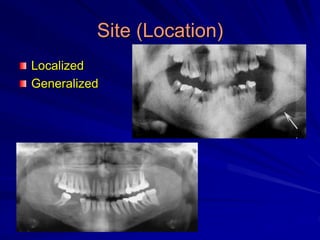

Site (Location)

Localized

Generalized

Multiple